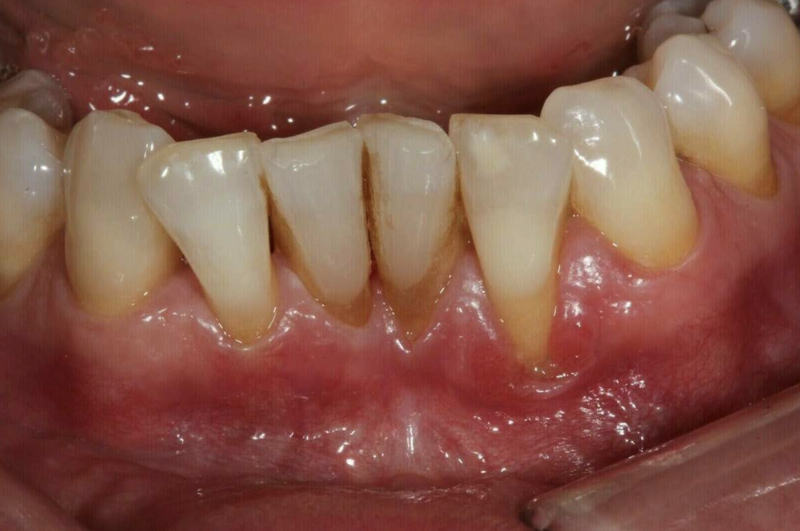

Dans le cas où on est en présence d'une récession gingivale et que celle-ci continue de progresser soit par la maladie parodontale soit par un brossage traumatique ou que le sensibilité thermique est importante et gênante, on peut greffer de la gencive et maintenir un environnement propice à l'hygiène.

Avant